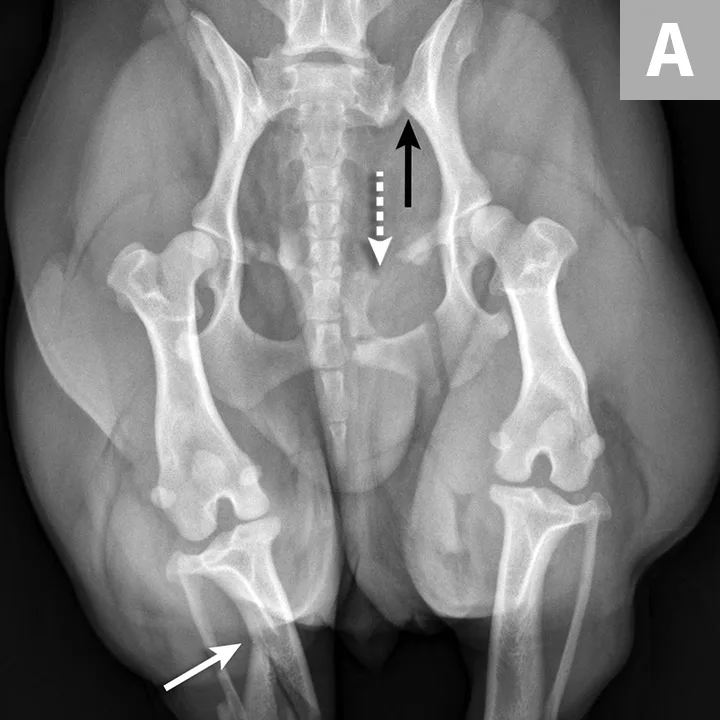

There are many different types of pelvic fracture configurations, and nearly half of pelvic injuries in dogs and cats involve fractures of the ilium.3,4,7,8 Clinically significant fractures involve the weight-bearing axis of the pelvis that includes the ilium and acetabulum (Figures 1-3). Although not a fracture, sacroiliac luxation is potentially significant because the sacroiliac joint is a component of the weight-bearing axis of the pelvis. Unilateral or bilateral fractures or luxations may occur, and it is common for patients to have a combination of pelvic injuries.3,4,7,13

FIGURE 1A

An 11-year-old intact female Welsh corgi with injuries of the weight-bearing axis of the pelvis. Ventrodorsal (A) and lateral (B) projection images show a left sacroiliac luxation with cranial and ventral displacement (black arrow). Pubic fracture with lateral displacement (dashed arrow) and an oblique tibial fracture (white arrows) were additional comorbidities. The tibial fracture was treated surgically with an internal plate fixation, and the pelvic injuries were managed conservatively.